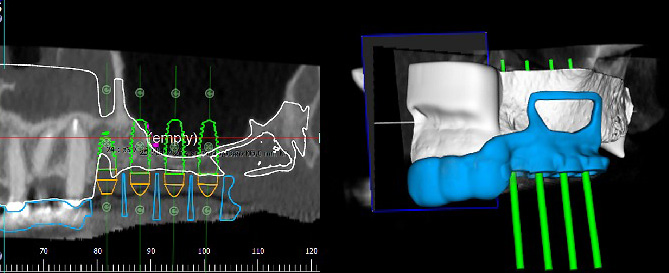

К сожалению, по нашим данным (Аванесов, Седов, Морданов и др, 2018) встречаемость признаков данной артерии на КЛКТ составляет 76%. При условии визуализации ААА на КЛКТ, после виртуального планирования расположения имплантатов, возможно спроектировать дизайн хирургического шаблона таким образом, чтобы можно было безопасно провести технику открытого синус-лифтинга (рис 2).

рис 2.jpg

Рисунок 2. Планирование положения имплантатов на КЛКТ.

Спроектирован дизайн шаблона, который также включает рамку для антротомии, разработанную в соответствии с протоколом операции.